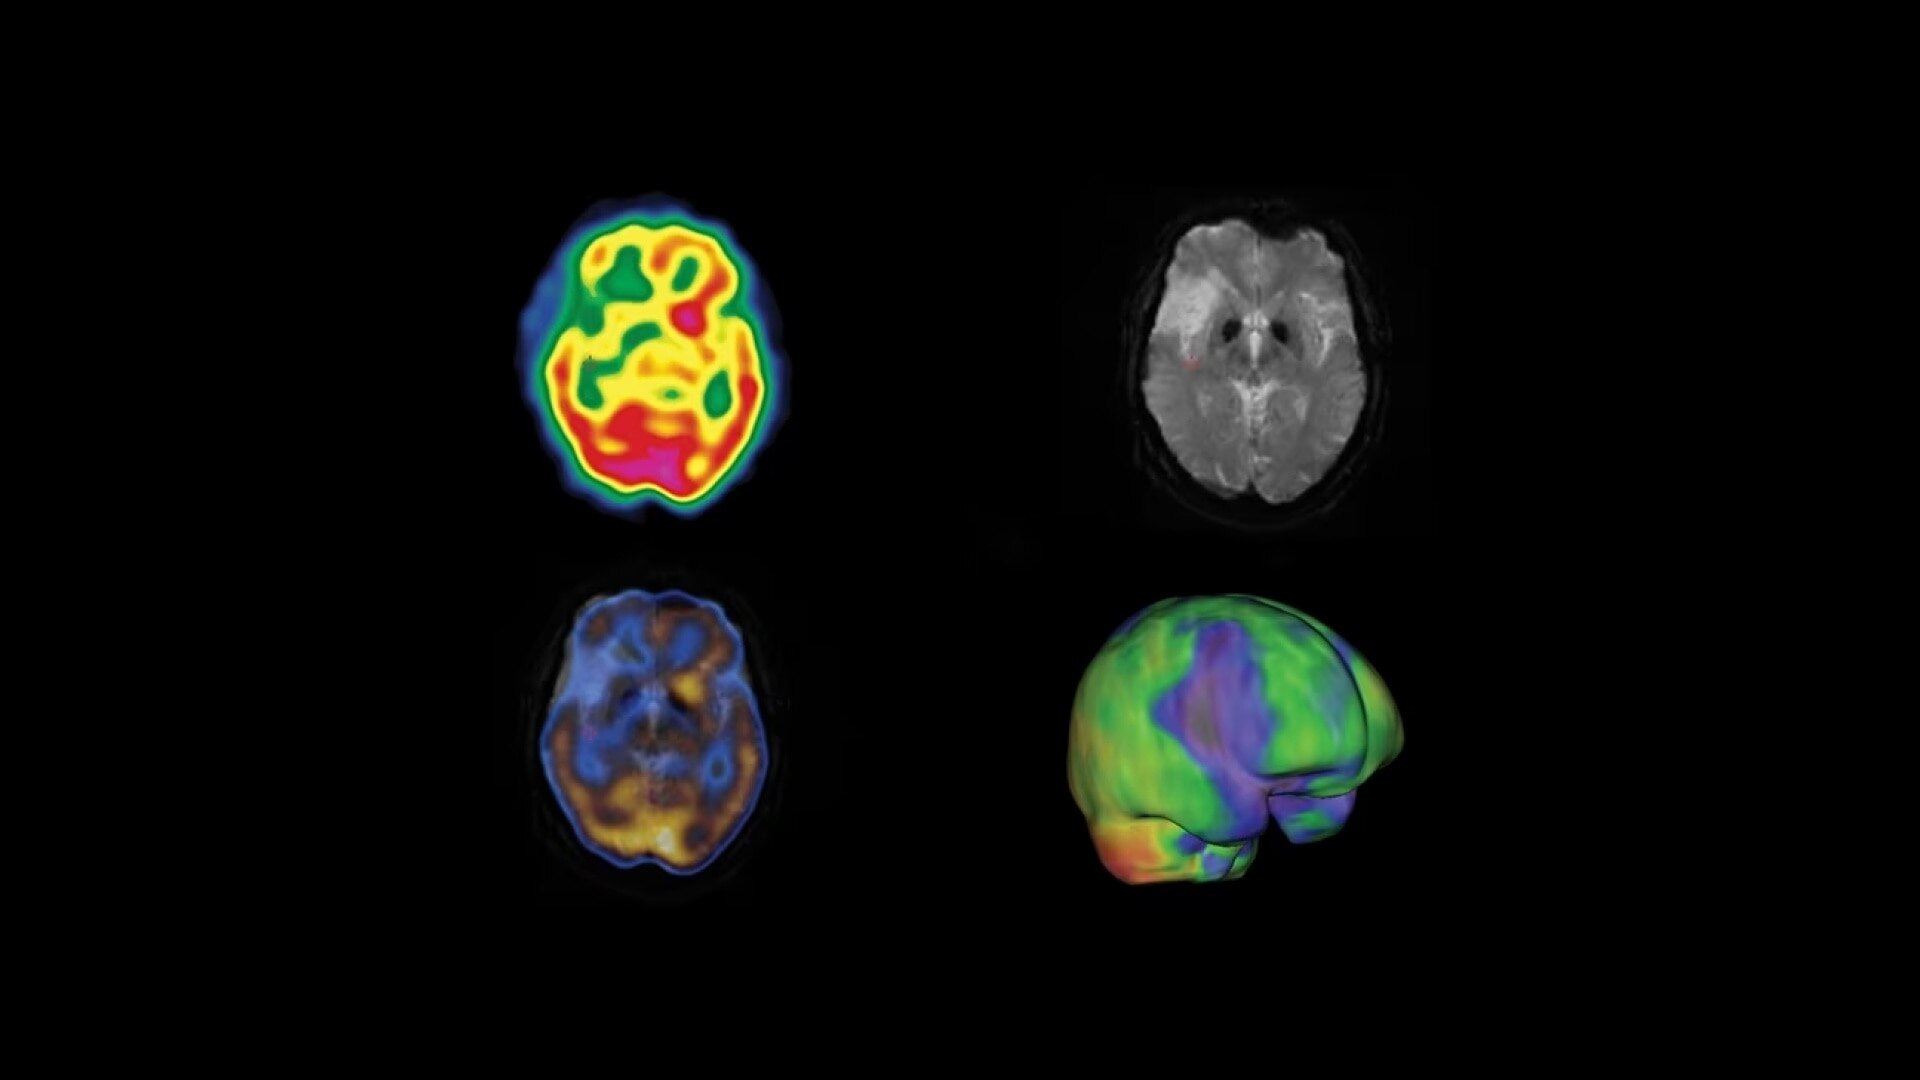

One home for all of your molecular images

SmartConsole makes advanced procedures more accessible by transferring exams directly to the PACS or other pre-defined DICOM destinations with no operator intervention, even if SPECT/CT fusion is not supported, by exporting the studies in DICOM PET format.

You can generate and send an additional dataset in PET DICOM format to enable quantitative SPECT results and SPECT SUV (Standard Uptake Value) on any PET DICOM compliant workstation or PACS. As a result, referring physicians can review and evaluate your SPECT/CT exams with the same quality of information they have come to expect from your PET/CT, as adjunct information to the original SPECT/CT images.